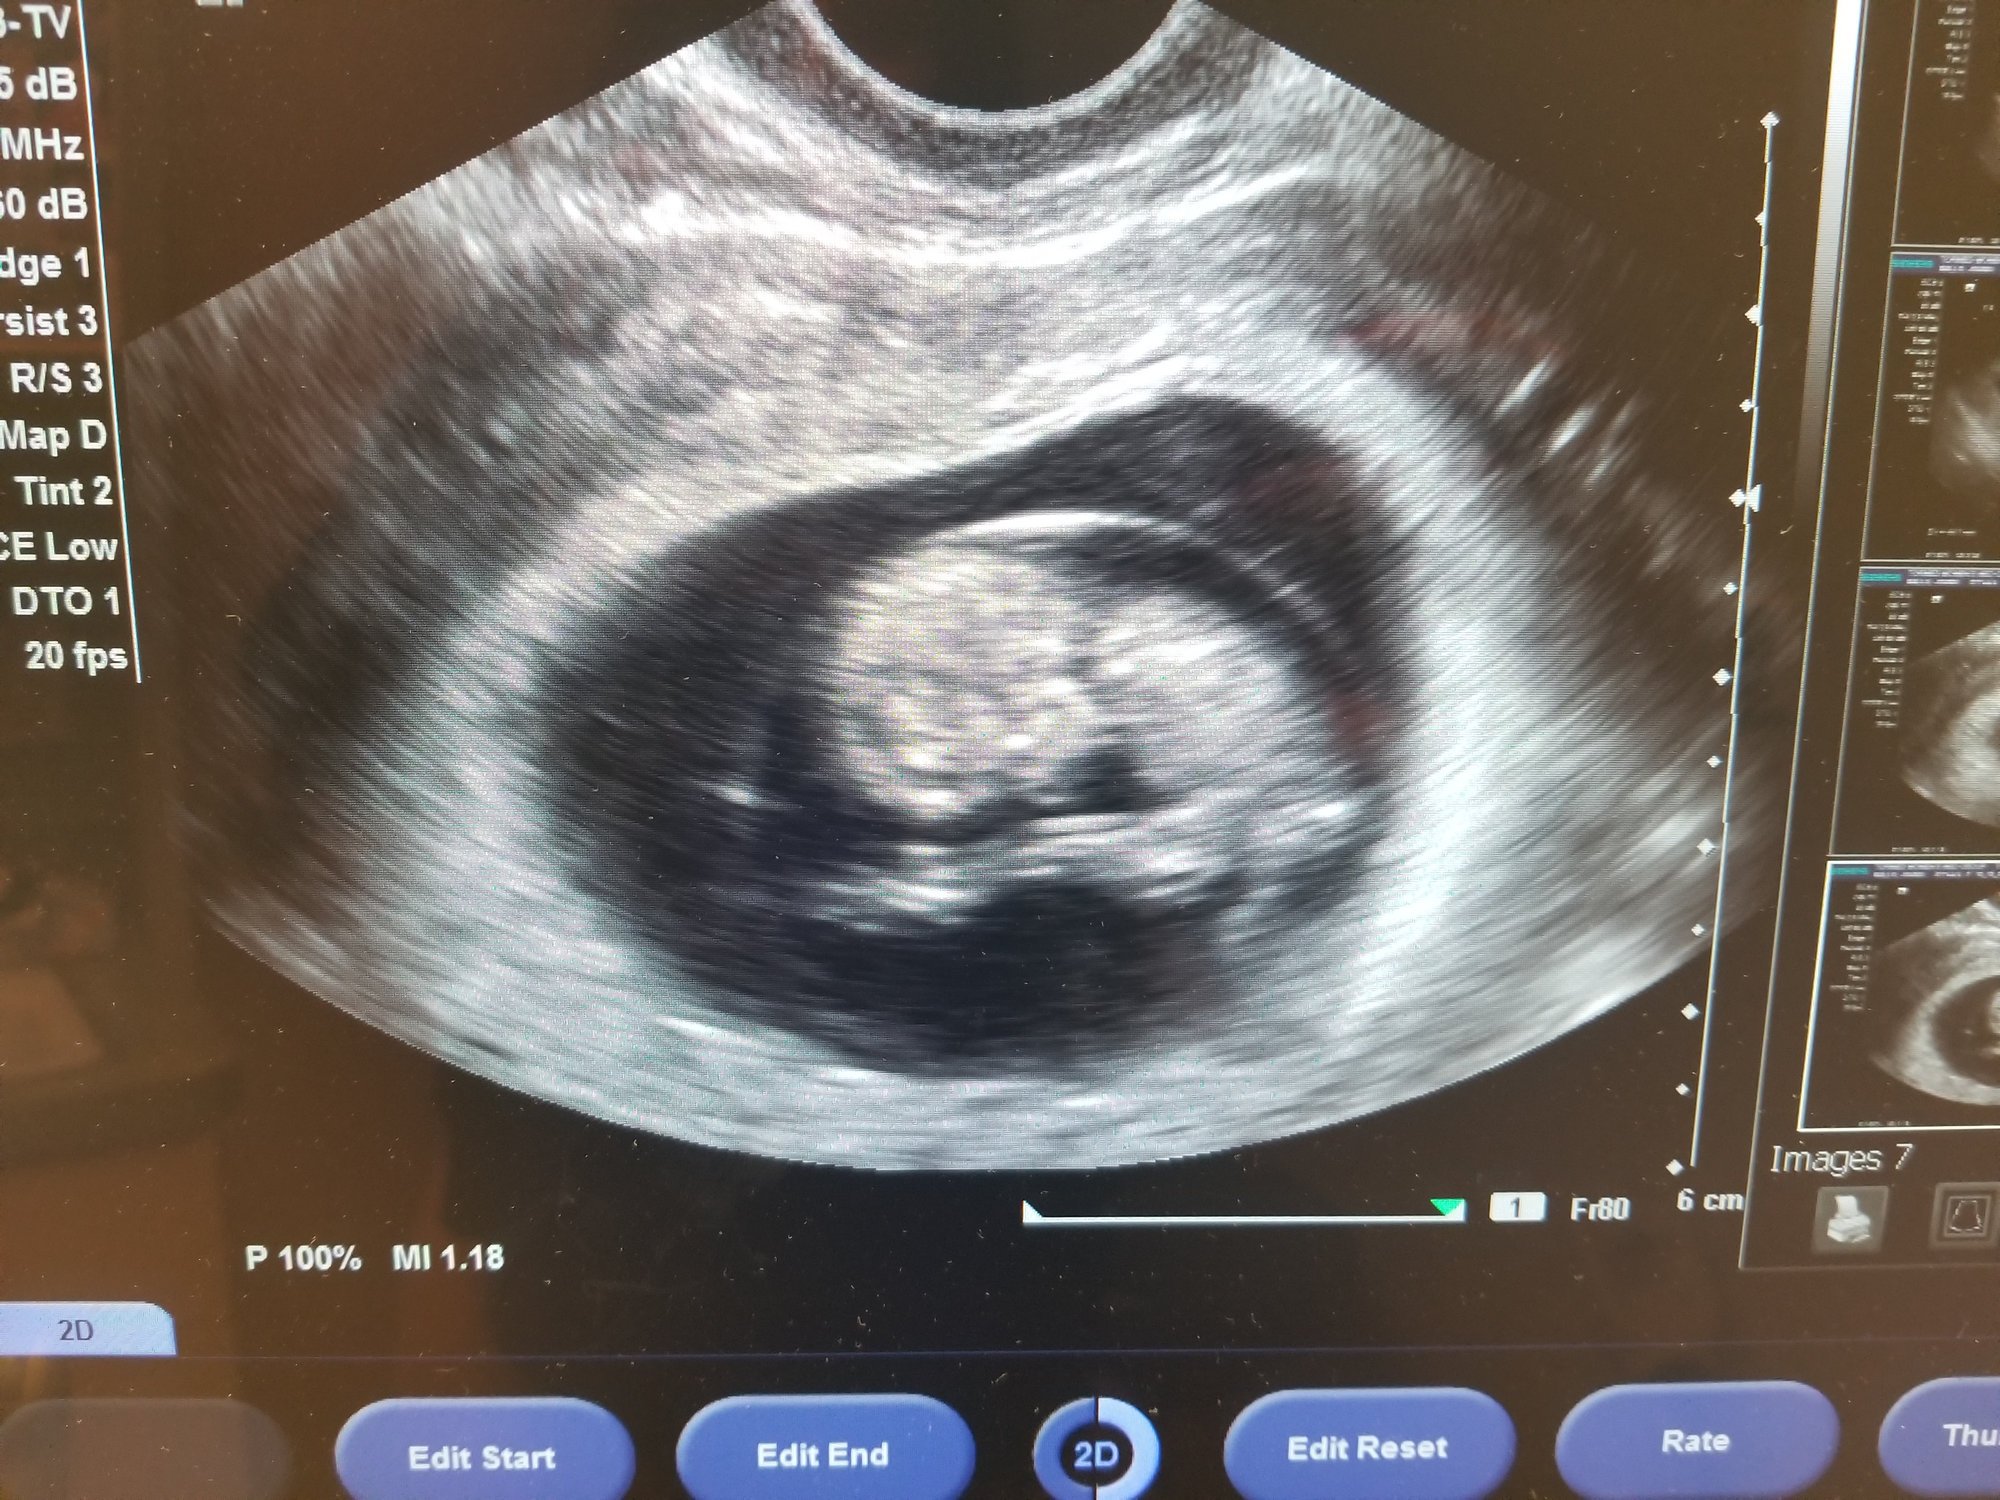

Went yesterday and measured 2 days ahead of schedule. Today I am 10w2d and my little tater tot looks like she/he likes to stretch or is practicing to be an olympic diver 😉😍

@mamajojo1981 this is the most adorable ultrasound!!